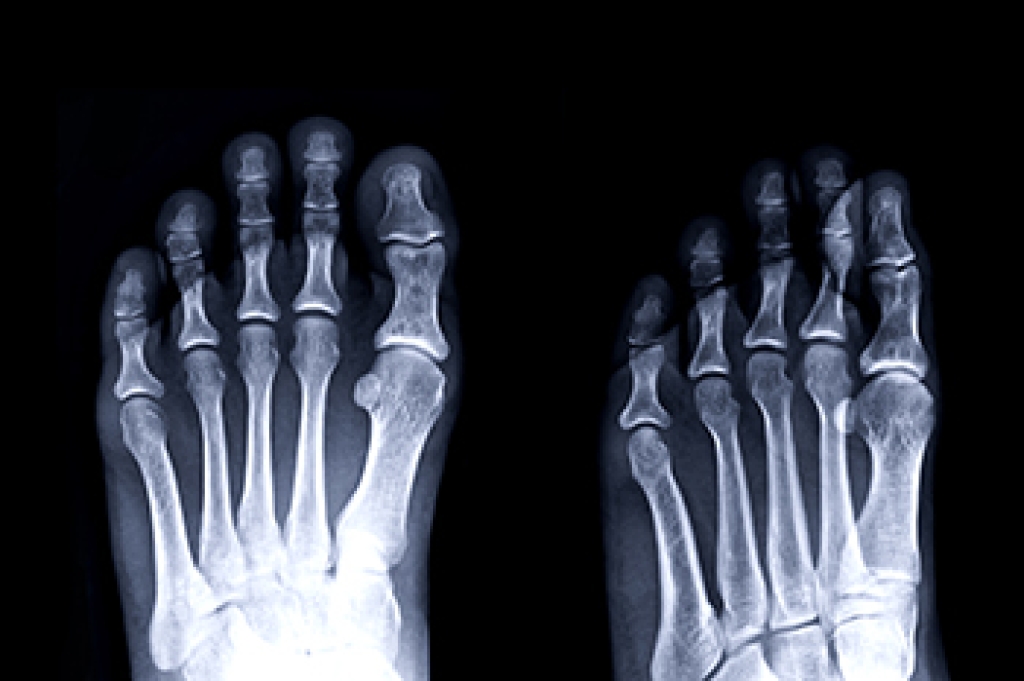

Diagnosis

Due to the wide variety of potential causes of ankle pain, podiatrists will utilize a number of different methods to properly diagnose ankle pain. This can include asking for personal and family medical histories and of any recent injuries. Further diagnosis may include sensation tests, a physical examination, and potentially x-rays or other imaging tests.

Treatment

Just as the range of causes varies widely, so do treatments. Some more common treatments are rest, ice packs, keeping pressure off the foot, orthotics and braces, medication for inflammation and pain, and surgery.